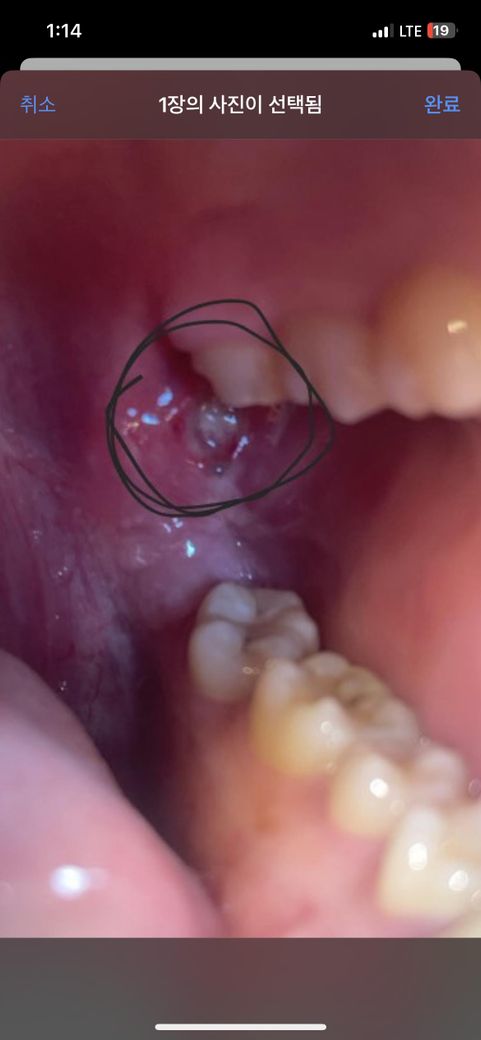

입을 벌릴때 아프고 환부를

자극할시 아프고침삼킬때 목쪽 근육이 아픈데 구내염일까요?평소 구내염이 잘 나기는 하는데 구강암일까 걱정되어서 질문드립니다.

올려주신 사진은 먼저 치아 손상으로 인한 구내염의 가능성이 생각됩니다. 이비인후과나 치과 진료를 받아보시기 바랍니다.

네 구내염으로 인해 안쪽으로 구강 내 궤양이 생긴 것으로 보입니다.

보통 그 위치에서는 음식물이 고여있거나 편도염과 관련하여 발생할

수 있으며 가글과 함께 항생제를 같이 복용하는 것이 좋습니다

사진을 보니 목 안쪽에 염증이 있는 것처럼 보입니다. 평소에 구내염이 잘 나는 체질이라면 이번에도 구내염일 가능성이 큽니다. 구내염은 스트레스, 면역력 저하, 영양 부족, 자극적인 음식 섭취 등 다양한 원인으로 발생할 수 있습니다. 구내염은 보통 1-2주 내에 자연적으로 치유되며, 통증 완화를 위해 진통제를 사용하거나 소금물로 가글링을 하면 도움이 될 수 있습니다.

구강암은 일반적으로 지속적인 통증, 출혈, 궤양, 혹은 덩어리가 있는 경우 의심할 수 있습니다. 현재 증상이 지속되거나 악화되고, 특히 통증이 심하다면 정확한 진단을 위해 치과나 이비인후과 전문의를 방문하는 것이 좋습니다.